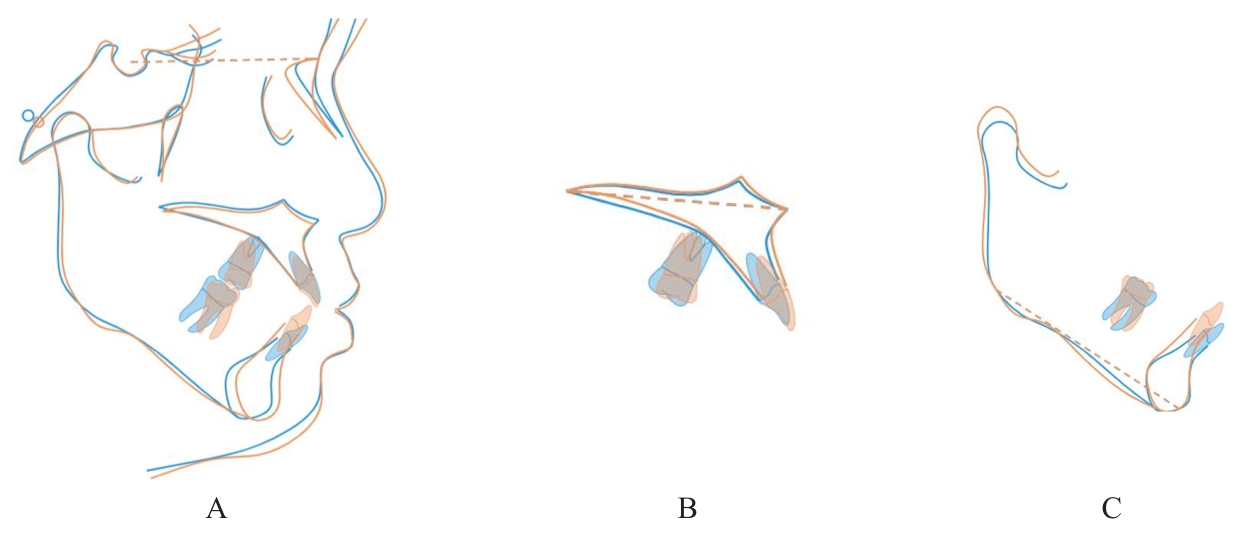

Grade Ⅲ open bite complicated with tongue hypertrophy treated by mandibular incisor extraction:A case report and literature review

Tab.1

Cephalometric detection analysis of patient with grade Ⅲ open bite complicated with tongue hypertrophy before and after treatment"

| Measurement | Normal (x±s) | Pretreatment | Posttreatment |

|---|---|---|---|

| SNA (°) | 82.8±4.0 | 84.1 | 83.8 |

| SNB (°) | 80.1±3.9 | 80.7 | 82.2 |

| ANB (°) | 2.7±2.0 | 3.4 | 1.6 |

| MP-SN (°) | 32.5±5.2 | 35.2 | 32.4 |

| U1-SN (°) | 105.7±6.3 | 116.9 | 111.8 |

| U1-NA (mm) | 5.1±2.4 | 6.7 | 6.6 |

| U1-NA (°) | 22.8±5.7 | 32.8 | 28.1 |

| L1-MP(°) | 92.6±7.0 | 105.7 | 93.4 |

| L1-NB (mm) | 6.7±2.1 | 8.7 | 6.8 |

| L1-NB (°) | 30.3±5.8 | 41.6 | 28.0 |

| U1-L1 (°) | 125.4±7.9 | 102.1 | 122.4 |

| Wits (mm) | -1.1±2.0 | -2.4 | -2.0 |

| APDI (°) | 86.0±4.0 | 80.8 | 85.5 |

| ODI (°) | 73.3±5.9 | 66.0 | 68.0 |

| S-Go (mm) | 80.0±4.0 | 79.7 | 82.1 |

| N-Me (mm) | 112.0±7.0 | 118.9 | 119.5 |

| S-Go/N-Me (%) | 63.0±2.0 | 67.0 | 68.7 |